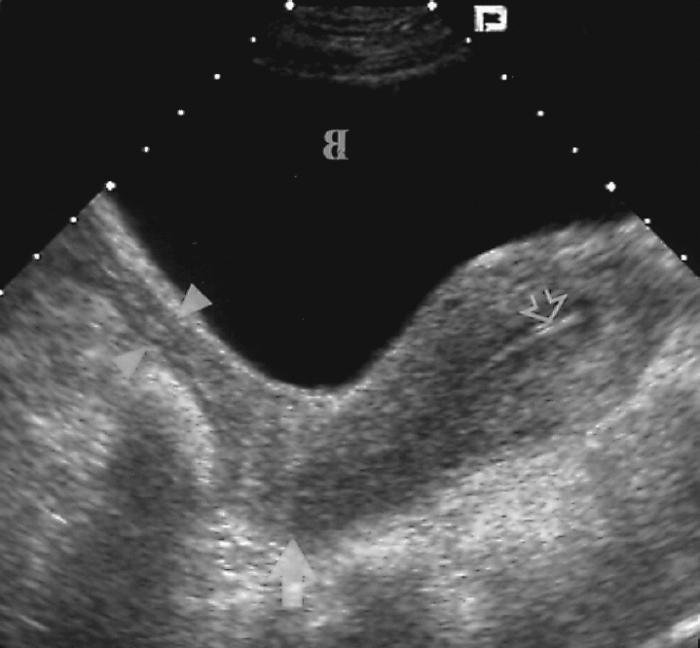

Медицинская диагностика: Гиперплазия эндометрия на УЗИ